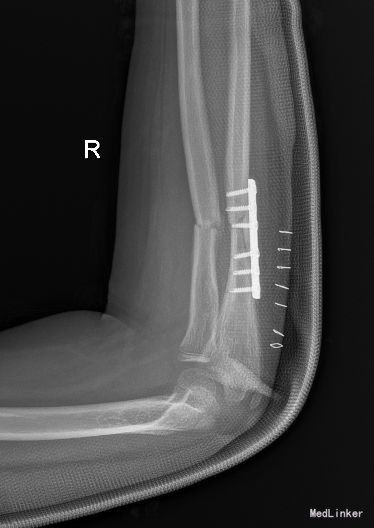

西医诊断:右尺桡骨骨折 治疗:全麻下行“右尺骨骨折切复内固定术”

后给予石膏外固定,抗菌素预防感染,促进愈合等药物治疗,适时换药、拆线并相关理疗。